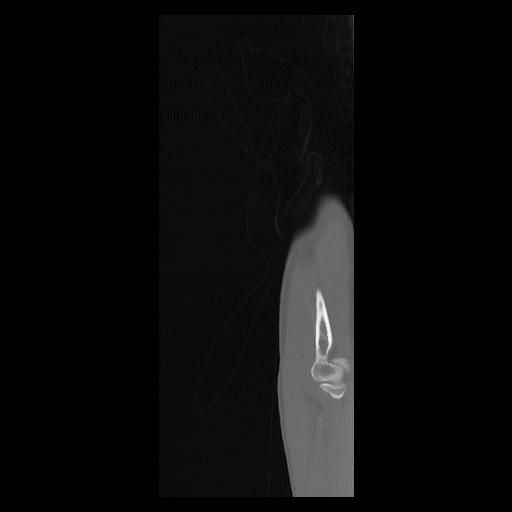

33 PULMON,CE,Sagittal,3.000,PULMON,Sagittal,